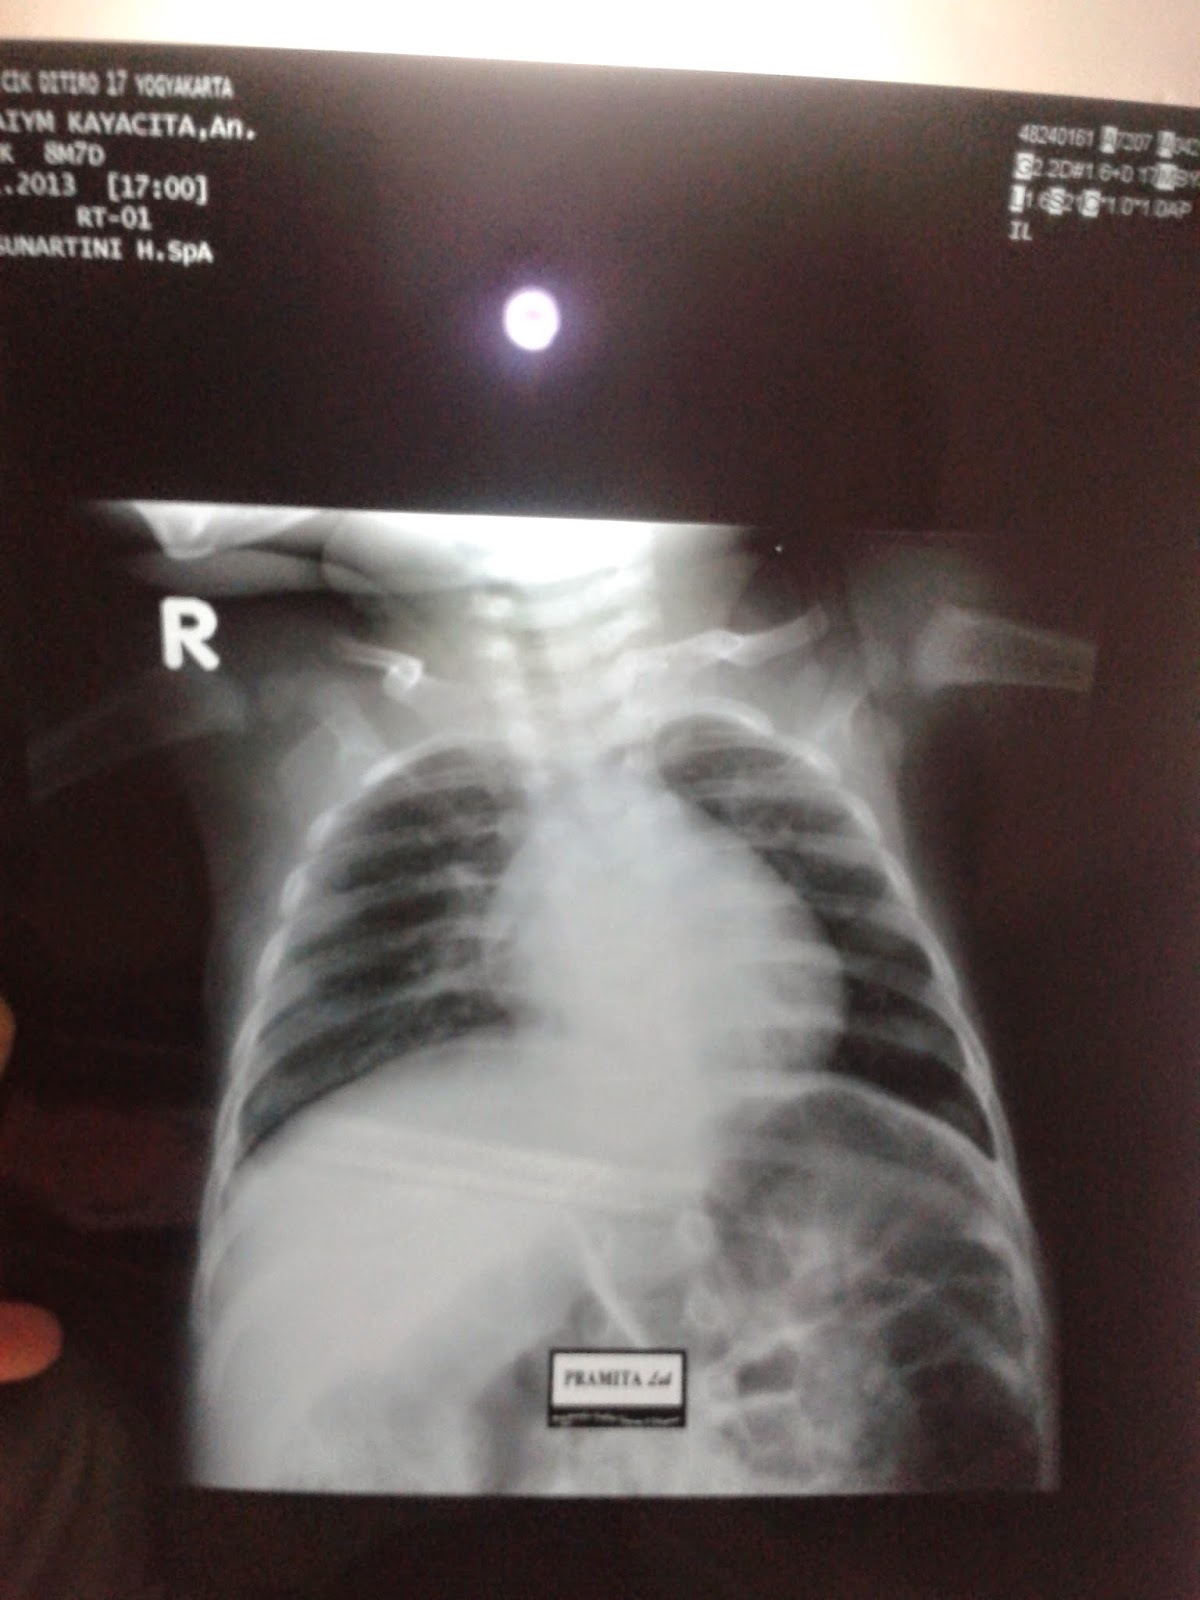

Gambar Tes Mantoux Negatif

Mengenal Lebih Jauh Tes Mantoux atau Uji Kulit Tuberkulin - Pasien Sehat Tes Dan Observasi TB - Mommies Daily Skrining Tuberkulosis, Interpretasi Tes Mantoux PPD, dan tes IGRA | by Wulunggono | Medium Cara Membaca Tes Kulit Tuberkulosis: 9 Langkah (dengan Gambar) Tes mantoux normal pada anak-anak. Sifat reaksi dalam tes diagnostik. Perawatan yang tidak benar pada area injeksi Dunia Anak: Test Mantoux Mantoux test - Wikipedia Tes Mantoux: Fungsi, Prosedur, Hasil, dan Risiko Cara Membaca Tes Kulit Tuberkulosis: 9 Langkah (dengan Gambar) Artikel Kesehatan - RSU Bhakti Rahayu Denpasar ASTRI DWIHARTARI TUBERKULOSIS. DEFINISI TB adalah penyakit menular langsung yang disebabkan oleh kuman TB (Mycobacterium Tuberculosis). Sebagian. - ppt download TB Membuat Kayyisah Menjadi Anak tak Biasa Tes Tuberkulin Reaksi manta hyperergic: konsep, makna, fitur pengambilan sampel, hasil, klasifikasi, efek samping dan kontraindikasi untuk - Obat-obatan 2020 Anak Rizla Atha Rayyan auf Twitter: “@drtiwi dok, setelah tes mantoux, benjolan diukur 2mm kl yg merah bulat 1cm apakah positif TB? Thx http://t.co/ZV58nkD3CS” Update Biaya Tes Mantoux untuk Pemeriksaan TBC | Daftar Harga & Tarif TATA LAKSANA TES MANTOUX March 2016 - dhaturembulan Tulisan ini adalah hasil rangkuman dari… - SAM - Sharing Asi-Mpasi | Facebook GUDANG ILMU: Cara Pemeriksaan Mantoux Tes Fungsi Tes Mantoux pada Anak dan Prosedurnya | Motherandbaby.co.id | LINE TODAY Memahami Fungsi Tes Mantoux dan Prosedur yang Dilakukan - Alodokter Tuberkulosis Pada Anak - Pasien Sehat 10 Cara Telaten Kenali dan Obati TB Laten - Opi Ardiani Mantouxtest Instagram posts (photos and videos) - Picuki.com Identifikasi Penyakit - ppt download Pitfalls” pada tb anak Mantoux Bunda Mazaya, Bila dan Adreena: TB PADA BALITA Tes Mantoux pada anak-anak dan orang dewasa: evaluasi hasil | Kompeten tentang kesehatan di iLive Tes Mantoux HUBUNGAN ANTARA GAMBARAN FOTO TORAKS DAN UJI TUBERKULIN PADA TB ANAK DI BALAI BESAR KESEHATAN PARU MASYARAKAT MAKASSAR PERIODE JULI JUNI PDF Free Download Pemeriksaan Mantoux test (tuberculin skin test) — Online Text Book ATLM Update Biaya Tes Mantoux untuk Pemeriksaan TBC | Daftar Harga & Tarif Skrining Tuberkulosis, Interpretasi Tes Mantoux PPD, dan tes IGRA | by Wulunggono | Medium Photo & Memories Tb 1 uwk 2010 dokter ngawurrrrrr | My Little Family Mantouxtest Instagram posts - Gramho.com Reaksi manta hyperergic: konsep, makna, fitur pengambilan sampel, hasil, klasifikasi, efek samping dan kontraindikasi untuk - Obat-obatan 2020 Cerita Berat Badan Liam Part 4 : Tes Mantoux – Nadia’s Tes Mantoux / Mantoux Test - Pusat Imunisasi RIWAYAT KONTAK TUBERKULOSIS SEBAGAI FAKTOR RISIKO HASIL UJI TUBERKULIN POSITIF - PDF Free Download Tes Mantoux untuk TBC, Prosedur, dan Memahami Hasilnya Bagaimana reaksi Mantoux dibuat. Reaksi mantoux pada anak-anak Apakah manta tidak berbahaya? RSIA Citra Ananda Reaksi mantoux pada anak-anak ukuran papula. Apa yang seharusnya menjadi reaksi Mantoux normal pada anak-anak? Penolakan untuk melakukan tes Prosedur Tes Menemukan Pasien TB yang Ternyata Putriku | gracemelia.com | Parenting Blogger Indonesia Tes Tuberkulin Hal Penting tentang Mantoux Test pada Anak | Popmama.com Reaksi manta hyperergic: konsep, makna, fitur pengambilan sampel, hasil, klasifikasi, efek samping dan kontraindikasi untuk - Obat-obatan 2020 Ketika Fitry Divonis TB - My Verandah Pitfalls” pada tb anak Cara Membaca Tes Kulit Tuberkulosis: 9 Langkah (dengan Gambar) Anak Sudah Berusia 3,5 Tahun Kok Masih 11 Kilogram, Dok? Halaman all - Kompasiana.com Pesat Jakarta ar Twitter: “Kenapa tes mantoux bisa positif palsu? #TBC https://t.co/baxEUfq6ju” Hasil Tes Mantoux Positive, Namun Igra Negatif Pada Anak Usia 1 Tahun - Tanya Alodokter TBAnak Instagram posts - Gramho.com Tes Mantoux TB Skin Test - Mantoux Method - YouTube Skrining Tuberkulosis, Interpretasi Tes Mantoux PPD, dan tes IGRA | by Wulunggono | Medium Tes Mantoux Cara Memastikan Penyakit TBC Anak-anak Pitfalls” pada tb anak Tes Mantoux Pada Anak Yang Terkontak Di Rumah Dengan Orang Dewasa Basil Tahan Asam Positif Atau Negatif Tuberkulosis Paru Yulianti Haratulisanah: Pengalaman Sakit TB Paru pada Anak Tuberculin Skin Test HUBUNGAN ANTARA GAMBARAN FOTO TORAKS DAN UJI TUBERKULIN PADA TB ANAK DI BALAI BESAR KESEHATAN PARU MASYARAKAT MAKASSAR PERIODE JULI JUNI PDF Free Download Tes Mantoux : Definisi, Cara & Penilaian TBAnak Instagram posts - Gramho.com TES TUBERKULIN. - ppt download Ketika Fitry Divonis TB - My Verandah Test Mantoux Tuberkulosis Simposium Online IDAI - Tuberkolosis Anak MANTOUX_TEST Pages 1 - 5 - Text Version | FlipHTML5 mantoux Instagram posts - Gramho.com Sop Test Mantoux Apakah saya perlu membuat manta per tahun. Apakah saya perlu membuat mantel bayi. Hasil Tes Mantoux Dan Status Vaksinasi BCG Pada Anak Terpajan TB Mengenal Tes Mantoux Untuk Mendeteksi Tuberkulosis Pada Anak Tes Mantoux Untuk Mendeteksi Tuberkulosis Pada Anak, Ini yang perlu Parents Ketahui | theAsianparent Indonesia Mycobacterium Tuberculosis – Welcome To My Life Mantouxtest Instagram posts (photos and videos) - Picuki.com MANTOUX_TEST Pages 1 - 5 - Text Version | FlipHTML5 Tuberculin PPD RT 23 SSI / jual cepat, exp oct 2020 | Shopee Indonesia Tes Mantoux - NT Health Digital Library Ketika Fitry Divonis TB - My Verandah Sop Test Mantoux Test Mantoux — Wikipédia March 2016 - dhaturembulan Tes Mantoux Untuk Mendeteksi Tuberkulosis Pada Anak, Ini yang perlu Parents Ketahui | theAsianparent Indonesia DOC) Skripsi Tingkat Pengetahuan Mahasiswa Mengenai Uji Tuberkulin 2010 | Ichwan Zuanto - Academia.edu Apa Bedanya Penyakit TBC pada Anak dan Dewasa? Lakukan manta dewasa. Apa reaksi negatif dan positif terhadap mantou. Hari apa setelah diaskintest. Tes tuberkulosis diaskintest Tes Mantoux mempredisi tanggapan terhadap Hal Penting tentang Mantoux Test atau Tes Penyakit TB pada Anak TBC Ppd Test Arabta - [PDF Document]